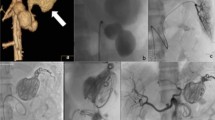

All aneurysms were successfully embolized using detachable coils alone, reaching a technical success rate of 100% (31/31). At the last follow-up, 24 (77.4%) aneurysms were completely occluded, and 28 (90.3%) achieved excellent clinical prognosis. No class I aneurysm deteriorated, but one class II aneurysm deteriorated to class IIIa. One class II aneurysm improved to class I; five class IIIa aneurysms improved to class I aneurysms; and one class IIIb aneurysm improved to class II. As summarized in Table 2, more class I aneurysms were identified at the last follow-up than immediately after embolization, and class IIIa aneurysms at the last follow-up became significantly fewer. No significant difference was noticed in either class II or IIIb aneurysms. In this study, a ruptured class II right RAA, determined on post-procedural angiogram, was embolized in an emergency setting (Fig. 2), whereas all other VAAs were embolized during elective procedures. Unfortunately, the ruptured RAA recurred after 2 years and after recoiling, it deteriorated to class IIIa at the last follow-up. Reintervention or recurrence was not found in any other cases.

Emergency embolization of a ruptured renal artery aneurysm (RAA). (A) Renal arteriogram demonstrated the ruptured RAA (arrow) with four efferent branches (arrowheads). (B) Renal arteriogram after coil embolization showed occlusion of the aneurysm with patent branches, and the classification of occlusion was classified as class II as per the Modified Raymond-Roy Classification (MRRC). (C) Two years later, recurrence of the aneurysm and increased contrast filling in the aneurysmal neck was detected on digital subtraction angiography (DSA). (D) DSA after re-embolization showed complete embolization of the aneurysm and classified as MRRC class I.